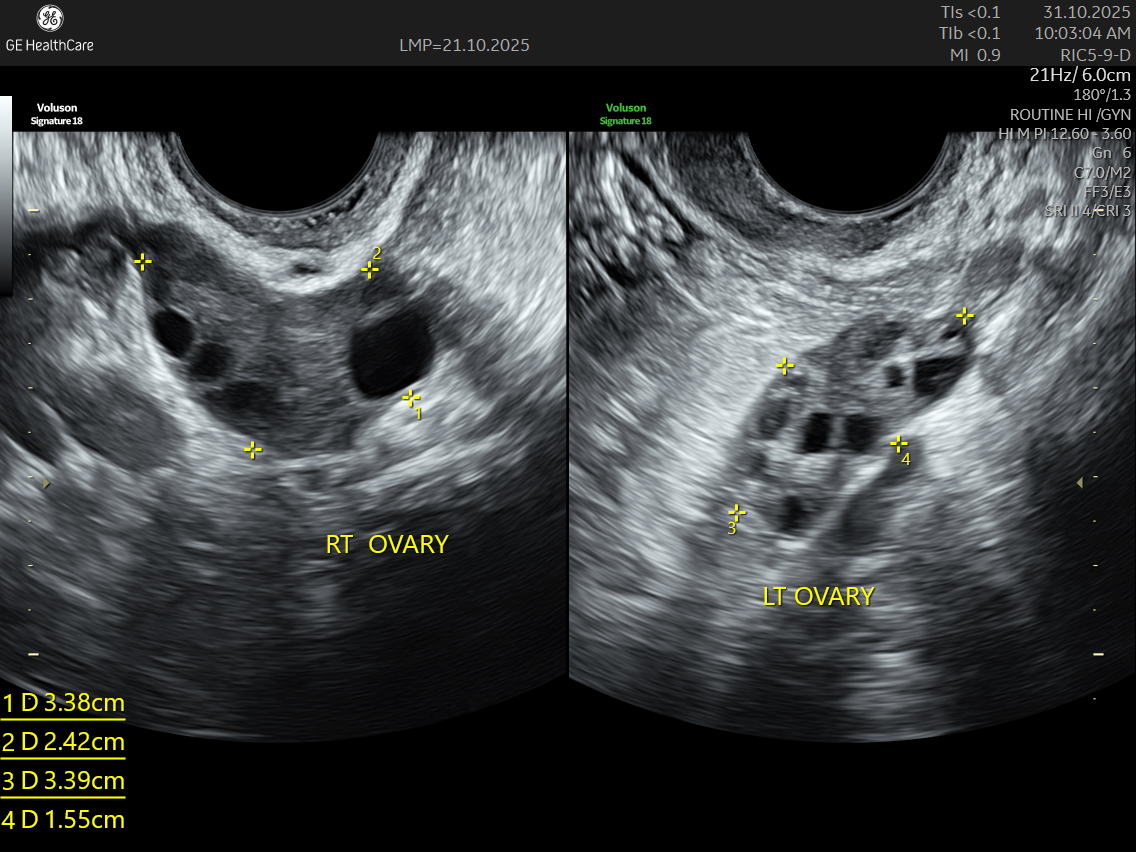

During an ultrasound, your doctor takes a close look at your ovaries to check three key things:

- Ovarian Size: Enlarged ovaries are common in PCOS, and measuring their size helps confirm if this is contributing to your symptoms.

- Follicle Count: The scan counts the number of tiny follicles around the edge of each ovary. A high follicle count is typical in PCOS and is an important diagnostic clue.

- Stroma Pattern: The texture and appearance of the ovarian tissue itself can show signs of the hormonal changes happening inside your body.